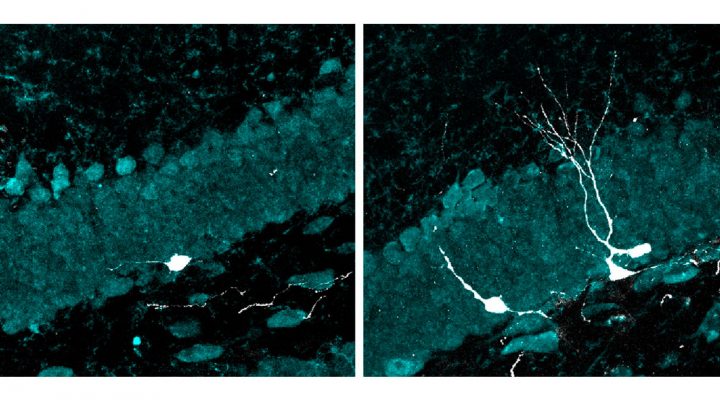

“Esas nuevas neuronas mostraron, además, un desarrollo más avanzado que las de los animales del grupo control: crecieron más, formaron dendritas y axones más complejos (los cables de entrada y salida de las neuronas) y establecieron conexiones más eficaces con el resto del circuito”, resalta la investigadora del CONICET Mariela Trinchero, autora principal del estudio junto a Magalí Herrero, becaria doctoral del CONICET, ambas integrantes del Instituto de Investigaciones Bioquímicas de Buenos Aires (IIBBA, CONICET-FIL) y del Laboratorio de Plasticidad Neuronal que lidera Schinder en la Fundación Instituto Leloir (FIL).

Pero no se conocen los mecanismos detrás de esos aparentes beneficios. Para investigar los efectos de la estimulación sensorial a 40 Hz sobre los circuitos neuronales, los equipos de investigación del CONICET y de la FIL trabajaron con ratones envejecidos que fueron expuestos diariamente a luz LED intermitente y a un tono auditivo de alta frecuencia a través de un parlante, que oscilaban a 40 ciclos por segundo. Luego, analizaron el hipocampo, la única región del cerebro que tiene la particularidad de generar neuronas a lo largo de toda la vida. Ese proceso, conocido como neurogénesis adulta, disminuye drásticamente con la edad.